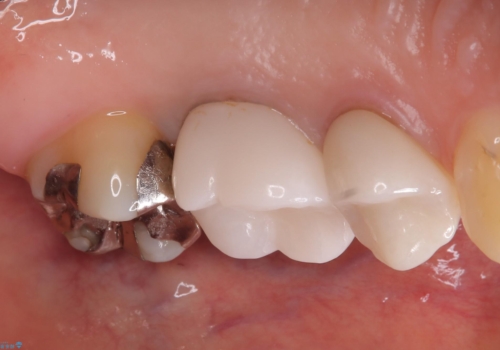

- 二次う蝕が心配という主訴で来院された患者さんです。

保険のメタルインレーは腐食しやすかったり、適合があまり良くなかったりで二次的にう蝕がインレー下で広がってしまうことが多々あります。

メタルインレーを除去したところ、残存歯質量が少なく破折のリスクを説明し、ゴールドクラウンでのやり替えとなりました。